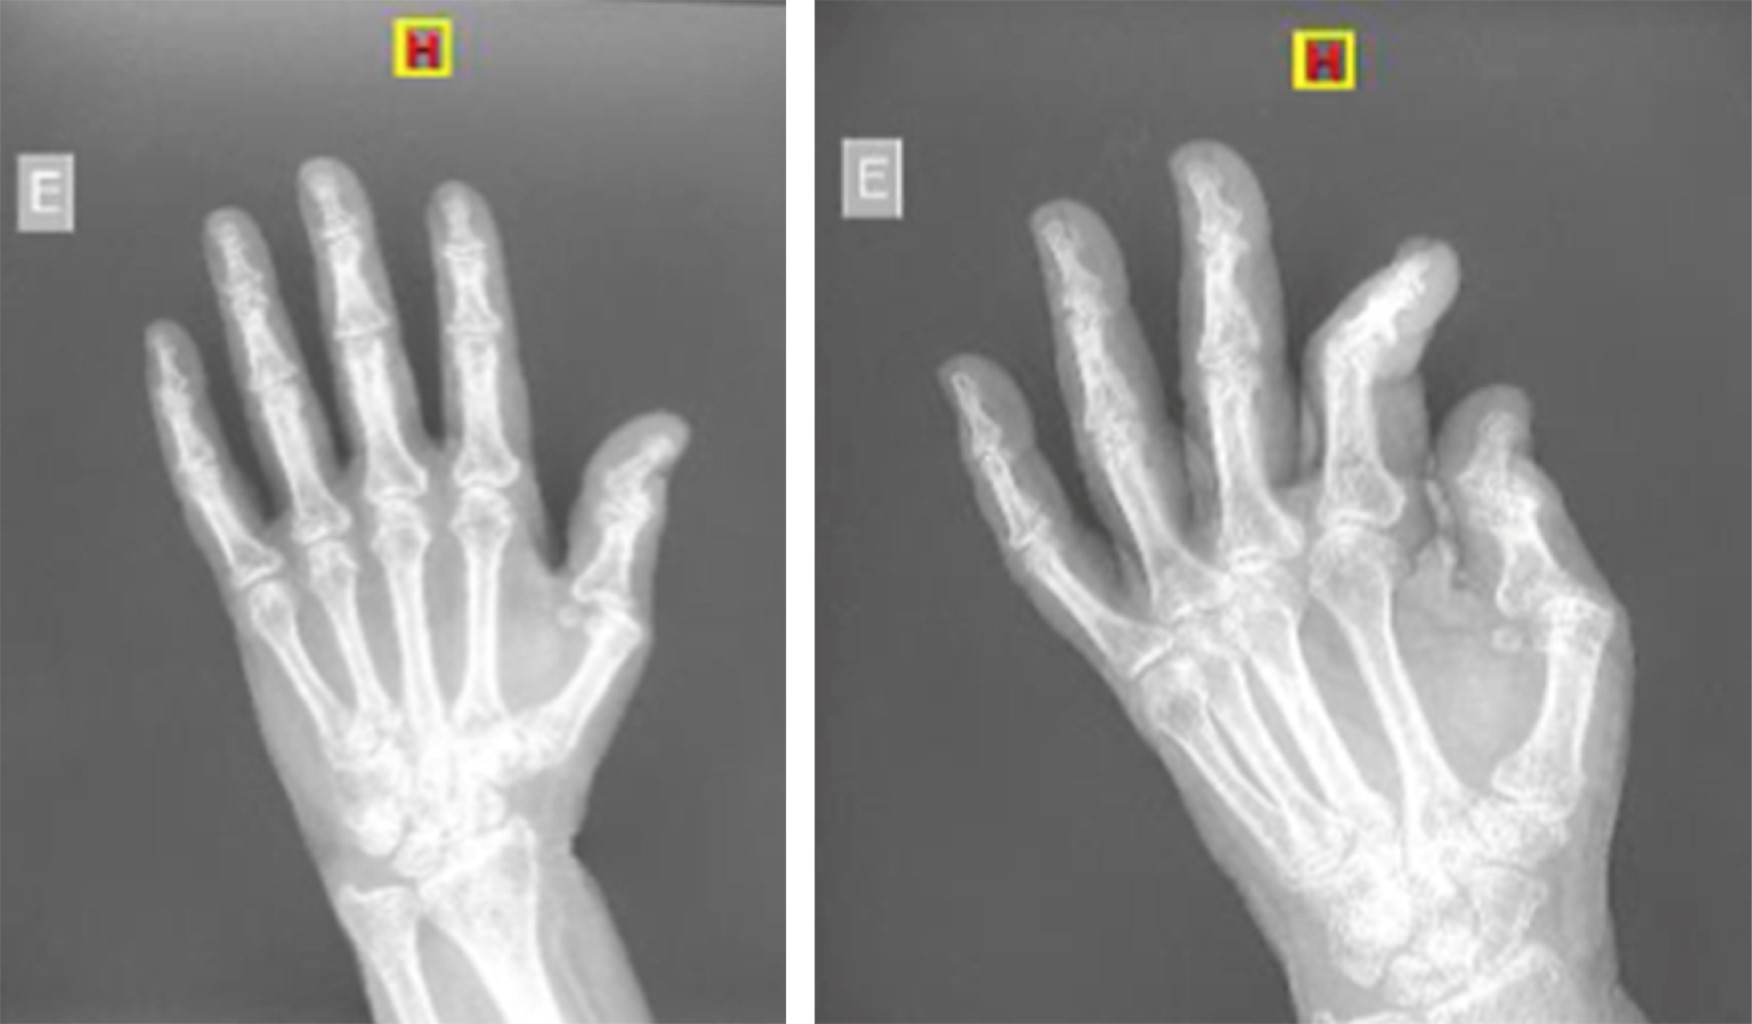

Luxación volar de la articulación metacarpofalángica del pulgar: reducción abierta y reparación del ligamento colateral cubital. Reporte de un caso

Introducción: las luxaciones metacarpofalángicas del pulgar no son lesiones muy frecuentes, es necesario conocer la anatomía de la región para conocer posibles causas de interposición que impidan una reducción cerrada de esta patología. Presentación del caso: presentamos el caso de una mujer de 75 años con luxación metacarpofalángica postraumática del pulgar que requirió reducción abierta y reparación quirúrgica. En este procedimiento realizamos reducción de la luxación, movilización de las estructuras interpuestas, reparación de la cápsula y reinserción del ligamento colateral cubital. El protocolo de movilización temprana ayudó a obtener muy buenos resultados. Conclusión: es imperativo considerar posibles lesiones asociadas durante la fase aguda para lograr resultados óptimos a corto, mediano y largo plazo para nuestros pacientes. Un enfoque integral y proactivo del diagnóstico y tratamiento es vital para abordar eficazmente esta patología y minimizar sus posibles secuelas.

Figura 2